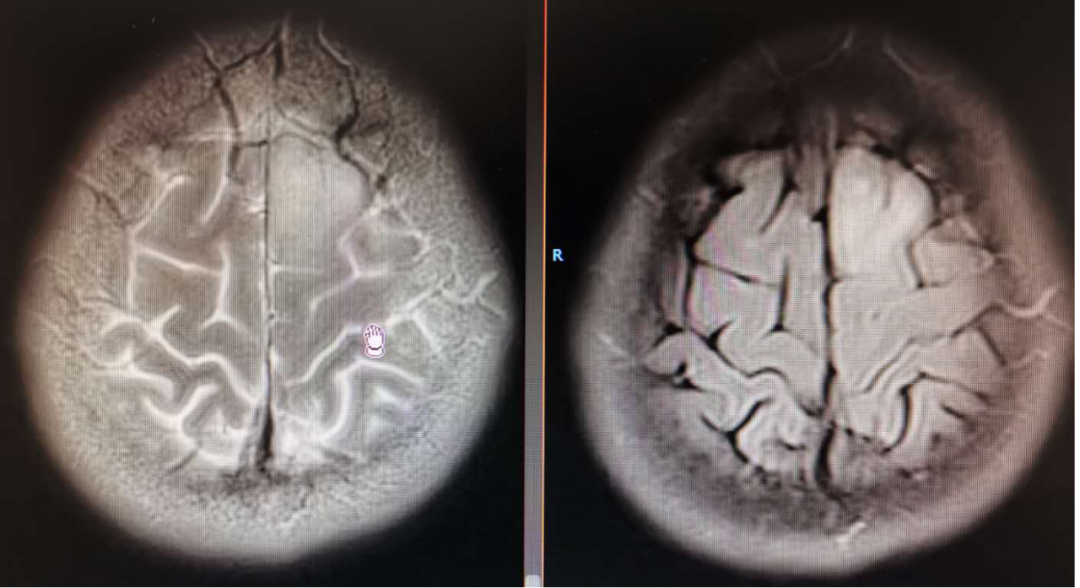

从术前核磁上看左侧额顶叶水肿范围较大,但是从增强上看似乎有强化,内囊前肢前上方有占位, Cho显示是升高的,考虑是肿瘤改变。

术后MRI显示术区水肿余无特殊

2020-01-06放疗后MRI

复查MRI提示:局部病灶强化,PWI提示局部灌注有缺失,考虑病情进展,同时不除外假性进展,患者脑水肿范围较大。